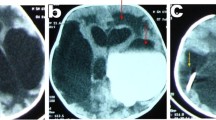

Communicating hydrocephalus was determined by computed tomographic cisternography (CTC) and/or cine-contrast image in MRI. In CTC, a small amount of contrast agent was injected by lumber puncture or from CSF reservoir if placed previously. CT scan was performed after 3, 6, and 24 h after the injection of contrast agent. When the contrast agent diffused both into all ventricular system and into cerebral surface, it was defined as communicating hydrocephalus (Fig. 1). In cine-contrast image in MRI, when CSF flow was observed both in the mesencephalic aqueduct and in the outlet of the fourth ventricle, it was defined as communicating hydrocephalus (Fig. 2). Patients without CTC or cine-contrast image in MRI were excluded from this study.